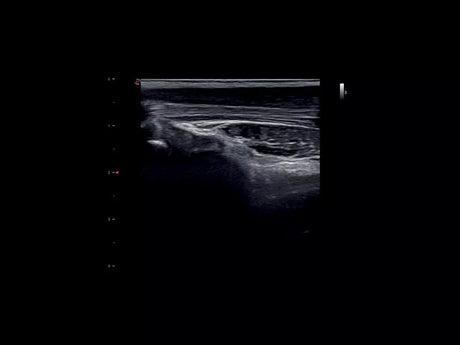

La qualité d’image est au cœur de la philosophie Esaote. Grâce à ses sondes de dernière génération et à son traitement du signal avancé, la marque permet une visualisation fine des structures anatomiques, même les plus profondes. Leurs échographes intègrent des écrans tactiles haute résolution, une interface claire et une connectivité complète, favorisant un flux de travail rapide et efficace.

Les échographes Esaote offrent une restitution d’image d’une grande précision, permettant un diagnostic fiable dans toutes les spécialités. Le traitement numérique optimise le contraste et la netteté, réduisant les artefacts et améliorant la détection des tissus pathologiques. Ces performances sont particulièrement appréciées en gynécologie, où la lisibilité des structures pelviennes ou obstétricales est déterminante.